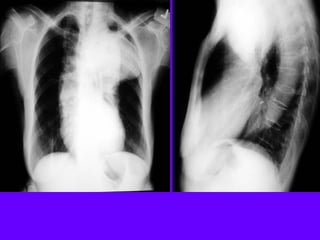

Aortic Aneurysms

• Location

– Ascending / Anterior mediastinum

– Arch / Middle mediastinum

– Descending / Posterior mediastinum

• Characteristics

– Mediastinal "mass" density

– Extrapleural

– Calcification of wall

• Dissecting

– Inward displacement of calcified intima

– Wavy margin

– Inlet to outlet shadow

– Left pleural effusion